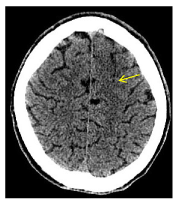

On day 14 of admission the patient developed acute neurological deficits: motor aphasia, conjugate gaze deviation to the left and an apparent right hemiparesis. Urgent cranial CT findings yielded up a subtle cortico-subcortical hypodensity in the left anterior frontal lobe with adjacent effacement of the sulci. There was an extension of the retropharyngeal abscess to both carotid spaces with enlargement and hypodensity within cervical and petrosal segments of the two internal carotid arteries (ICAs) which suggested occlusion due to septic thrombosis. (Figures 1, 2, 3, 4)

Figure 4.  Axial cranial CT shows subtle cortico-subcortical hypodensity in the left anterior frontal lobe with adjacent effacement of the sulci.